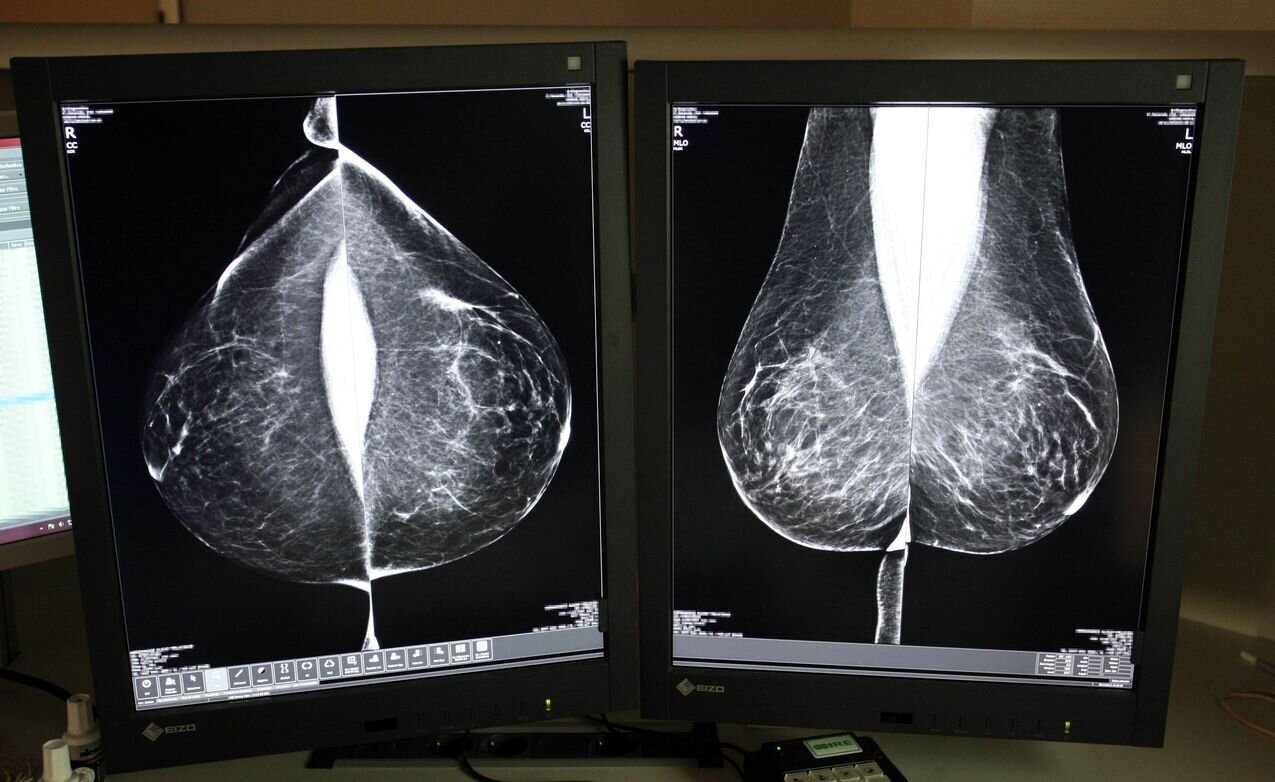

Estudio una mamografía digital, en el servicio de mamografías del Hospital Río Hortega de Valladolid. Foto: Rubén Cacho.

Desde su puesta en marcha en 1992, el programa se basa en el sistema de doble lectura, un protocolo que establece que cada mamografía sea evaluada por al menos dos radiólogos, de forma independiente, aumentando así la fiabilidad de los diagnósticos. Sin embargo, aumenta la carga de trabajo y plazos, motivo por el cual Sacyl ha optado, de nuevo, por externalizar el servicio al que el año pasado dedicó casi cuatro millones.